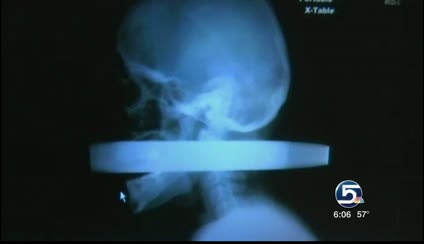

The X-ray taken of Linn's head right after his car crash five months ago is stunning. You can clearly see the pipe piercing his head.

Linn saw that image Tuesday for the first time.

"You can kind of see on my nose here, it came in here and went through it, and it came out the back right here," he said, gesturing to his face.